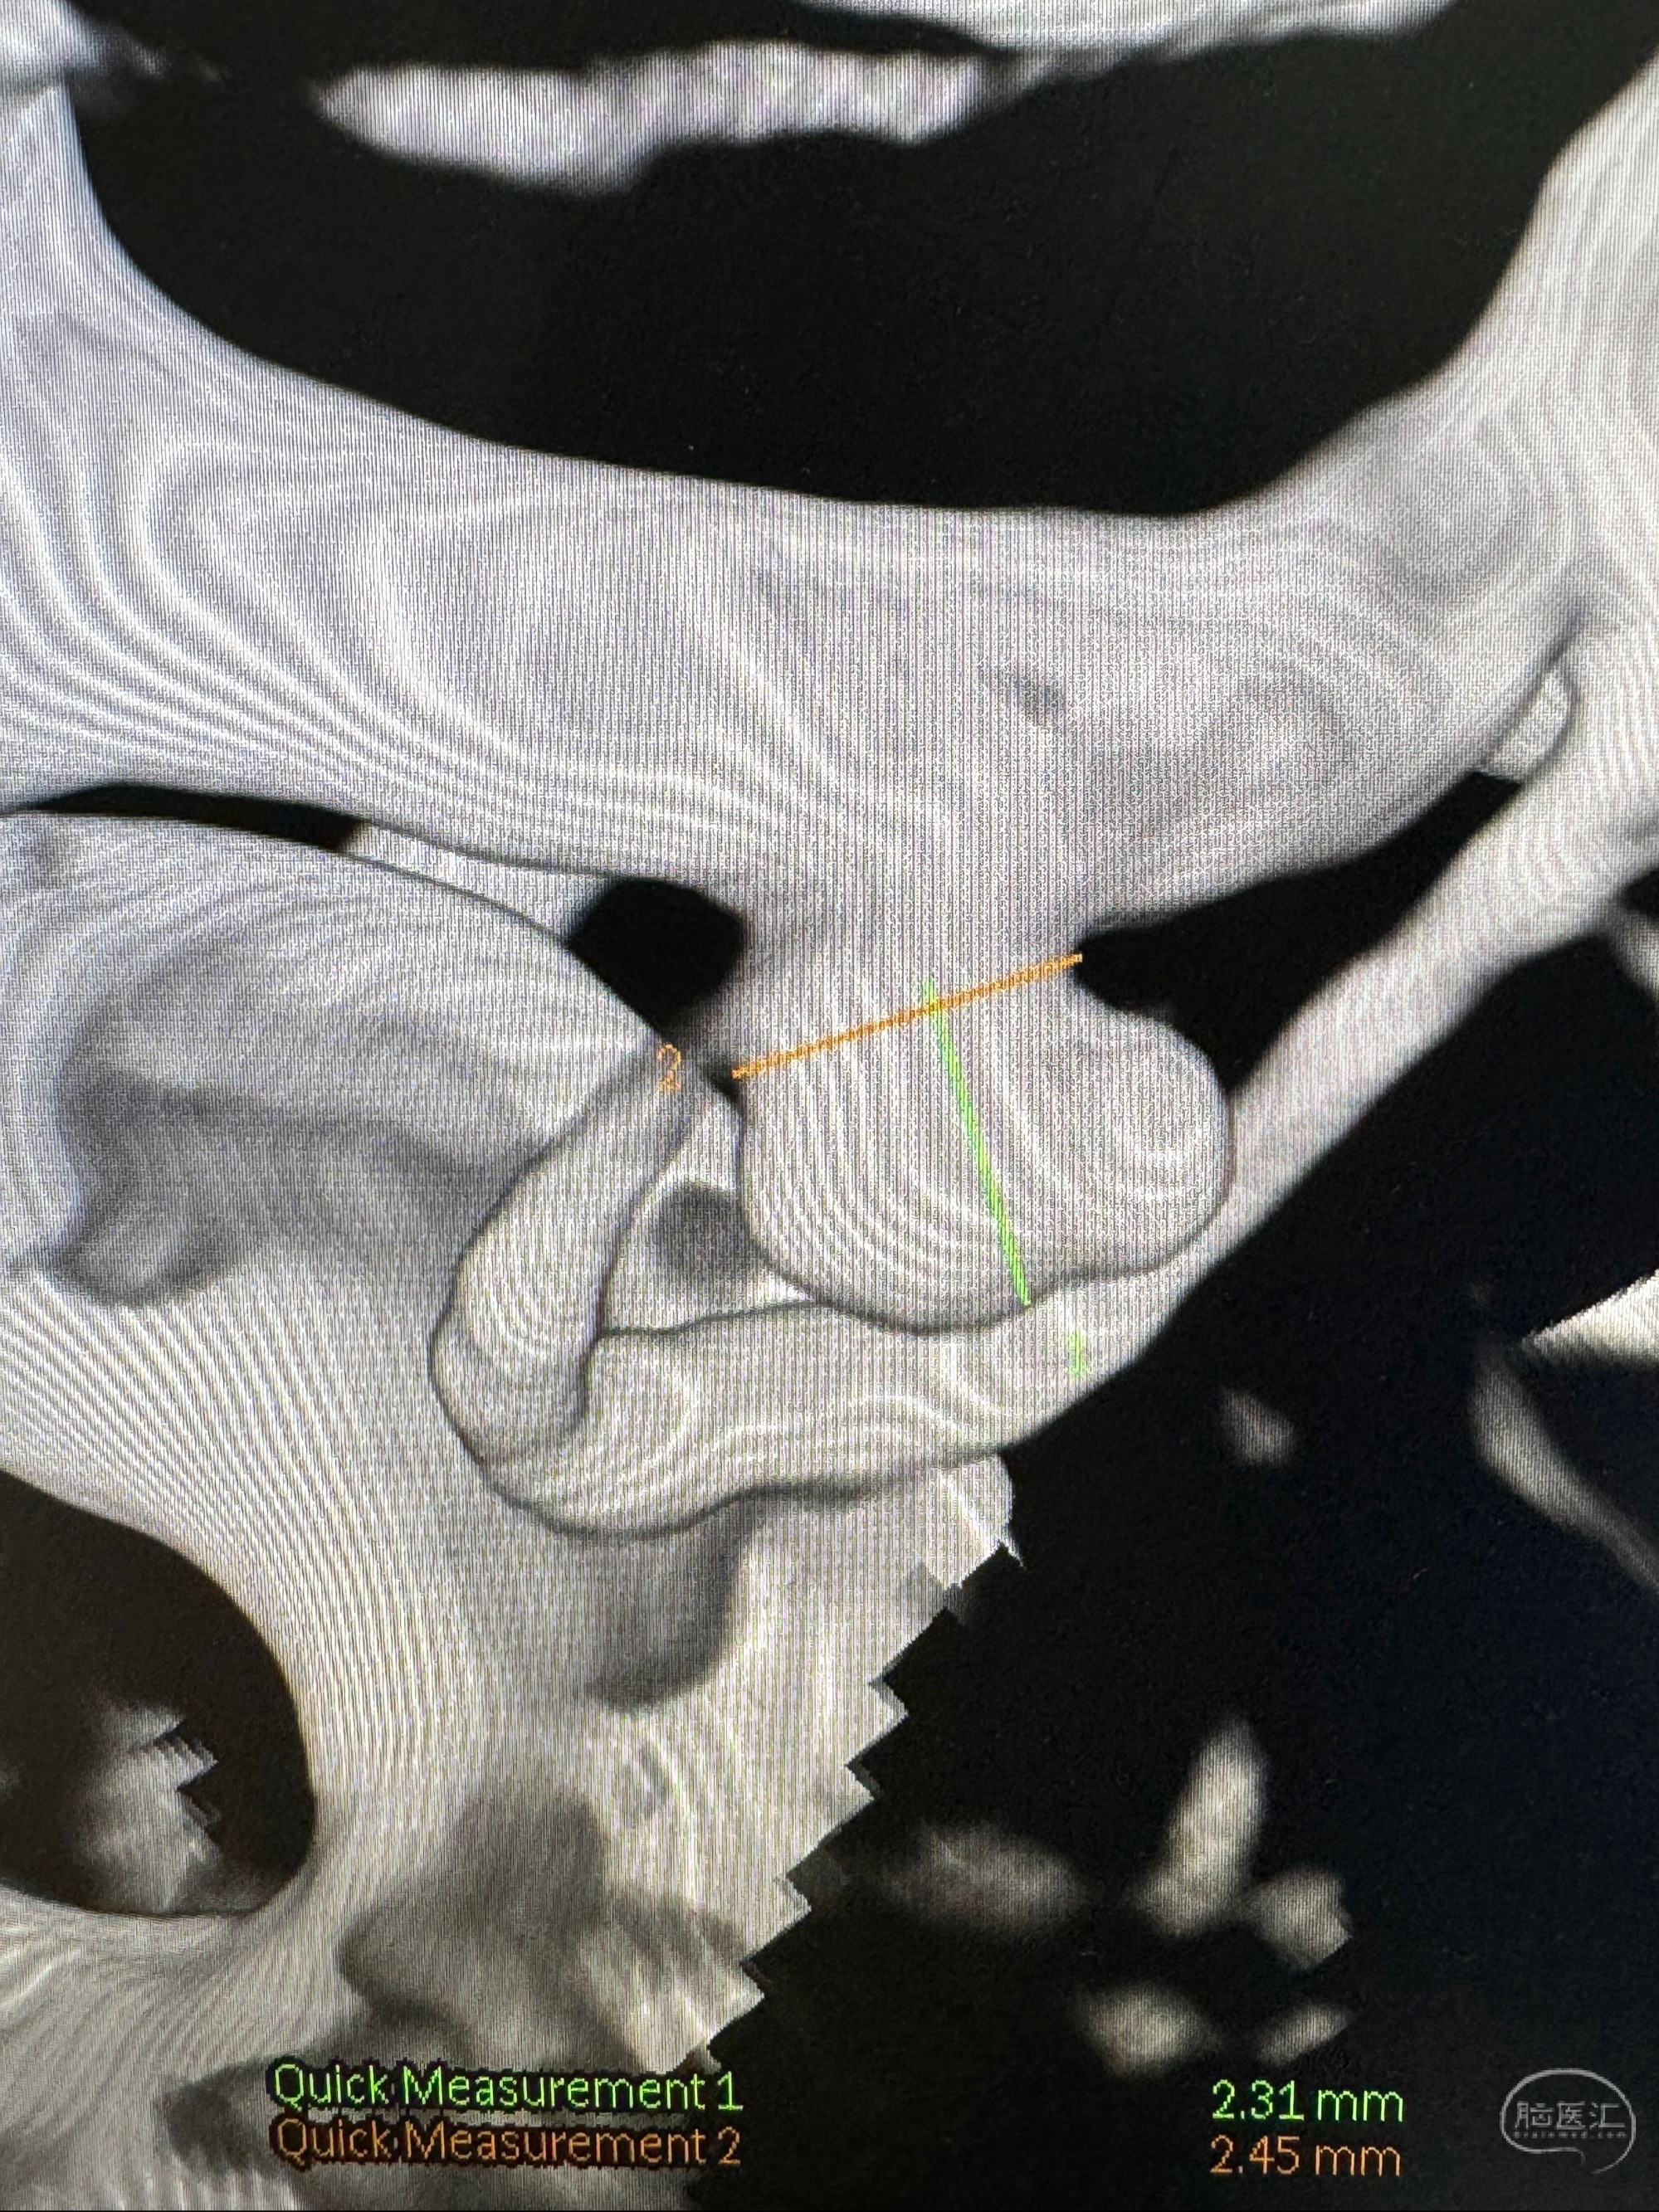

2023-11-24DSA:右侧大脑中动脉下干起始部动脉瘤,约2.3*2.5mm,形态规则